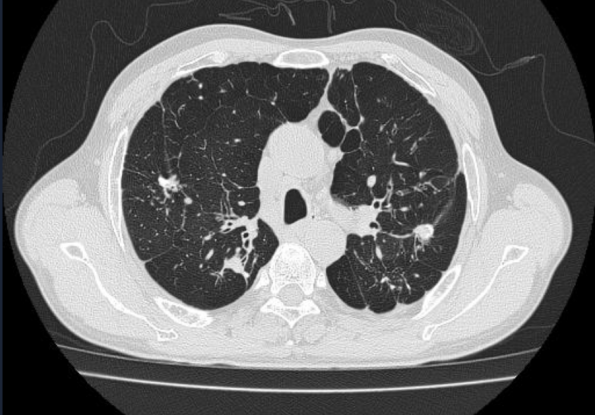

· 病例概况55岁男性,长期吸烟,慢阻肺4年余,长期吸入激素,因咳嗽咳痰气促加重入院治疗。查抗结核抗体IgG弱阳性,抗酸染色阴性,完善肺泡灌洗液病原体tNGS及结核抗体检测明确诊断肺结核。

△胸部CT可见双肺慢性炎症,双肺肺气肿,双上肺肺大疱

· 发病关联吸烟、慢性气道炎症、肺功能下降、气道结构破坏、长期使用激素,导致机体对结核防御能力减弱。

肺结核感染会进一步破坏肺组织,加重肺功能损伤,形成恶性循环。

因此慢阻肺和肺结核互为危险因素,谁为因果,需要详细结合病史及肺功能等进行鉴别